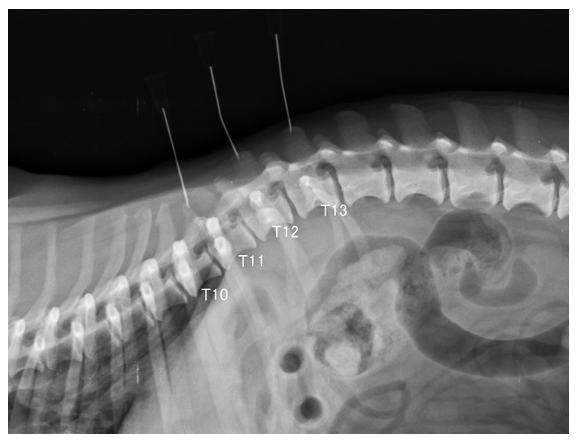

La columna presenta un buen alineamiento.

Lesión extradural lateralizada a la derecha en T11-T12, compatible con extrusión discal (hernia Hansen tipo I) con extensión del material discal cranealmente, a lo largo del cuerpo vertebral de T11 causando moderada/severa mielopatía compresiva.